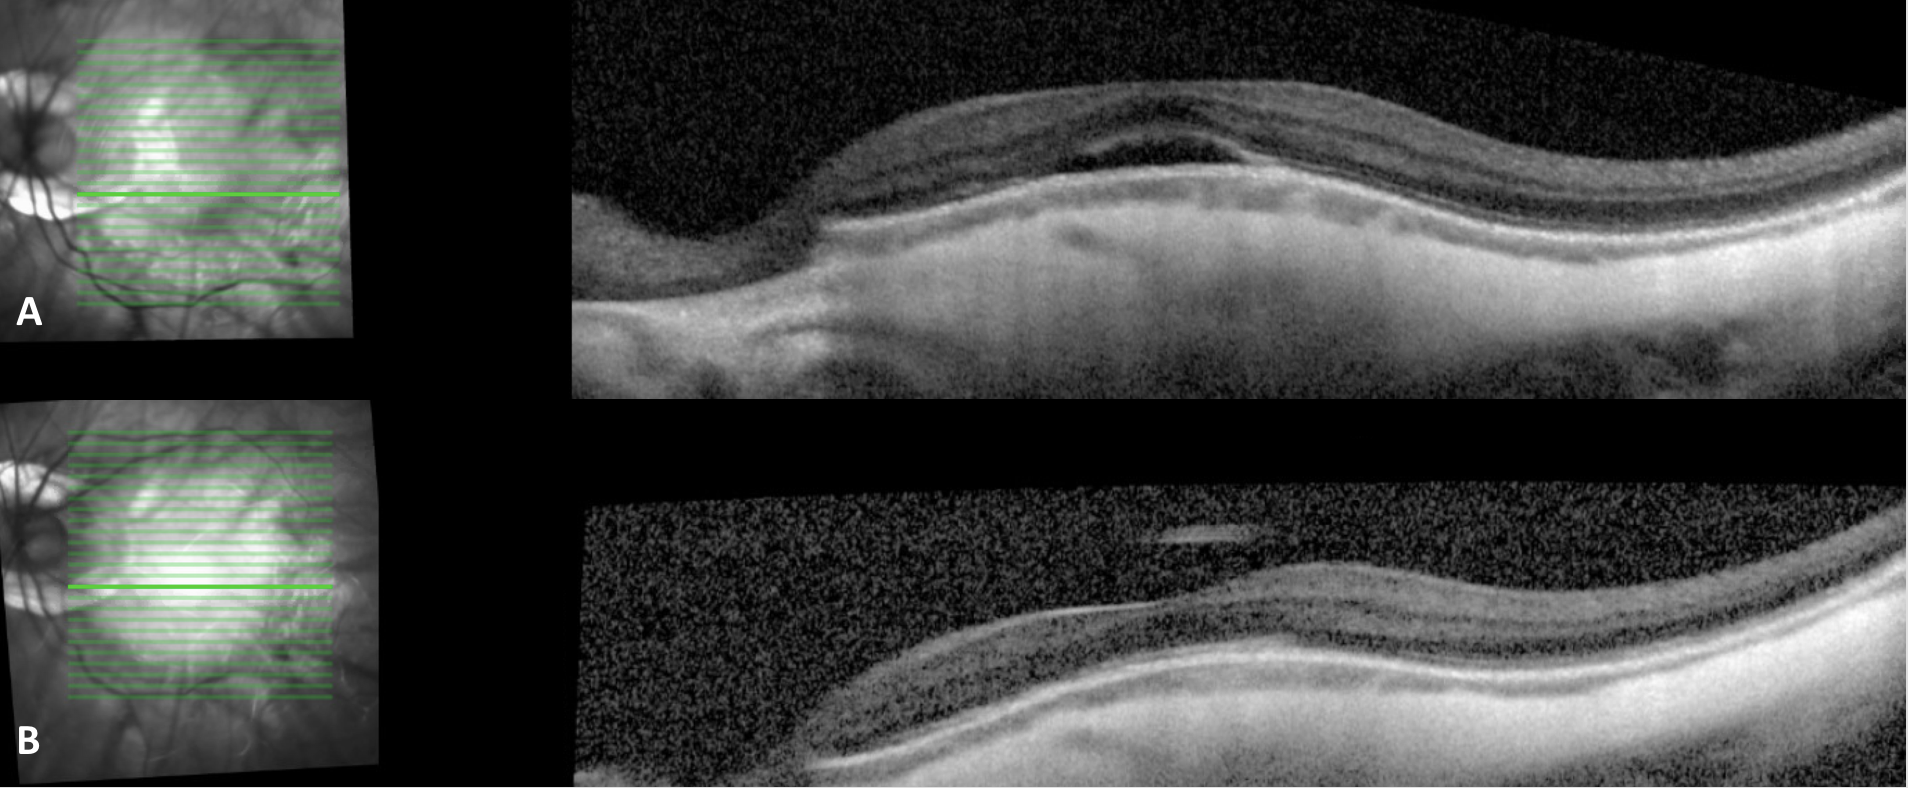

Optical coherence tomography through the macula, left eye, of a 26 year myopic (-20.00) male with A) a dome shaped appearance to the subfoveal macula with subfoveal subretinal fluid, a thin choroid, and thickened sclera. B) 3 months later, OCT demonstrates resolution of the subfoveal subretinal fluid and reconstitution of the foveal contour. Significant peripapillary atrophy can also be noted in the infrared images.